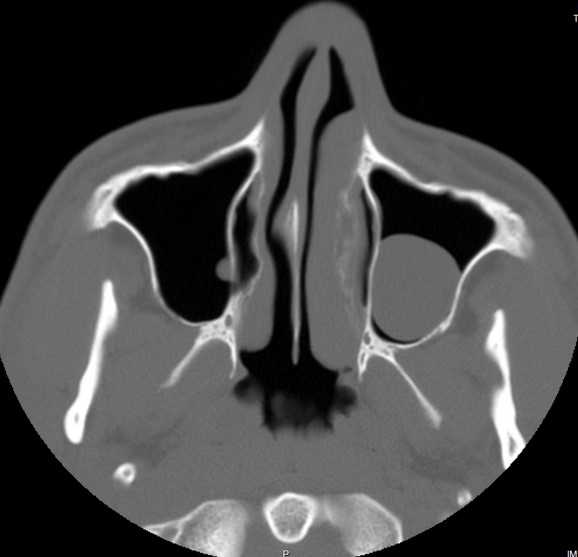

Когда речь идет о гайморовых пазухах, киста является одним из возможных диагнозов. Киста представляет собой опухоль, образованную жидкостью и обычно небольшого размера. Она может возникнуть в гайморовых пазухах, которые находятся по обе стороны носового перегородки. Киста гайморовой пазухи может быть причиной дискомфорта и некоторых симптомов, таких как головная боль и нарушение носового дыхания.

Киста гайморовой пазухи – это полость, заполняющаяся жидкостью и образующаяся в области гайморовой пазухи. Она может вызывать некоторые неприятные симптомы и представлять определенные проблемы для пациента. Но какой код присваивается этому конкретному диагнозу? В соответствии с МКБ-10, киста гайморовой пазухи имеет свой уникальный код, который помогает идентифицировать и классифицировать эту проблему. Данный код используется для учетных и статистических целей, а также для обработки и анализа данных.

Код диагноза для кисты гайморовой пазухи может быть представлен, например, как J32.4. Каждая цифра и буква в коде имеет свое значение и несет информацию о специфических характеристиках данного диагноза. Расшифровка кода позволяет медицинским профессионалам и статистикам узнать тип, локализацию и другие важные аспекты данного заболевания. Это также помогает установить связь с другими сопутствующими диагнозами и определить наиболее эффективные методы лечения и ухода за пациентом.